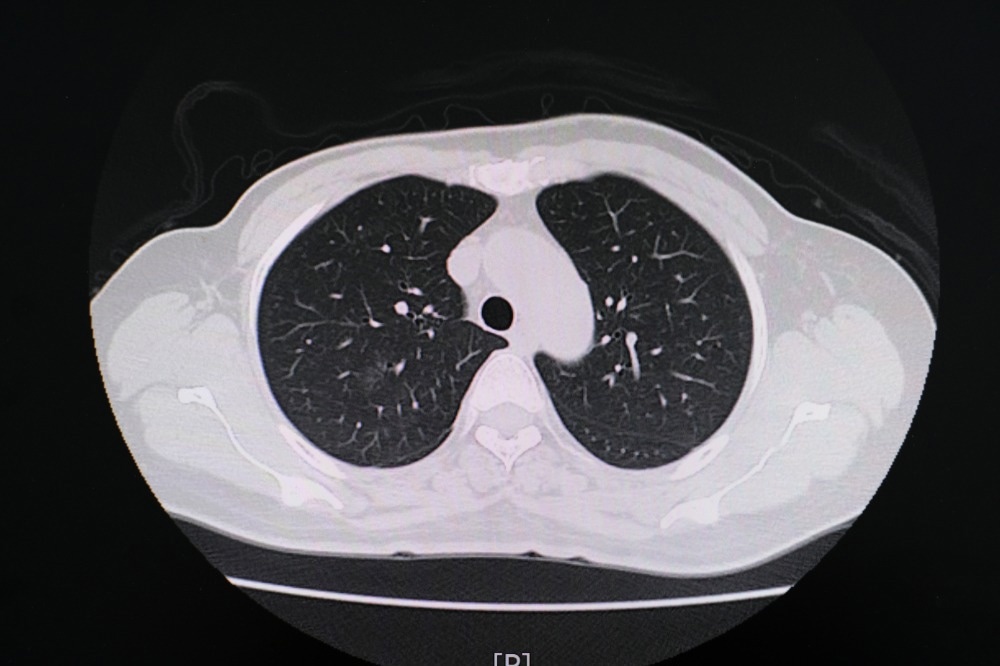

In einer kürzlichen Radiologie In einer Fachzeitschrift-Studie berichten Forscher aus der Thorax-Computertomographie (CT), dass die Lunge von Marihuana-Rauchern signifikantere Werte von Entzündungsmarkern der Atemwege und Emphyseme aufweist als die von Rauchern, die nur Tabak rauchen.

Lernen: Thorax-CT-Ergebnisse bei Marihuana-Rauchern. Bildnachweis: PIJITRA PHOMKHAM / Shutterstock.com

Neben Lungenfunktionstests kann auch die CT-Lungenbildgebung wichtige Informationen über die Auswirkungen des Marihuana-Rauchens auf die Lunge liefern.

Im Vergleich zu Nichtrauchern zeigten die CT-Befunde für Marihuana-Raucher unterschiedliche Raten von Emphysemen, Bronchialverdickungen, Bronchiektasen, mukoiden Impaktionen und zentrilobulären Knötchen, die alle CT-Marker für Atemwegsentzündungen sind. Gynäkomastie wurde auch bei 38 % der Marihuana-Patienten im Vergleich zu 16 % der Nichtraucher berichtet.

Beim Vergleich der CT-Ergebnisse zwischen Marihuana- und Tabakrauchern berichteten die Forscher von Unterschieden in der Bronchialverdickung, Bronchiektasie und mukoiden Impaktion. Darüber hinaus wurden bei gleichaltrigen Marihuanarauchern höhere Emphysemraten von 93 % bzw. 67 % bei ausschließlichen Tabakrauchern beobachtet. Beim Vergleich des Auftretens von zentrilobulären Knötchen zwischen Marihuana- und reinen Tabakrauchern wurden keine Unterschiede beobachtet; Dies kann jedoch auf die hohe Rate von Tabakrauchern zurückzuführen sein, die auch Marihuana rauchten.

Ein paraseptales Emphysem wurde auch häufiger bei Marihuana-Rauchern festgestellt als in den Lungen von Rauchern, die nur Tabak rauchten. Umgekehrt wurde ein zentrilobuläres Emphysem hauptsächlich in den Lungen von Tabakrauchern sichtbar gemacht.